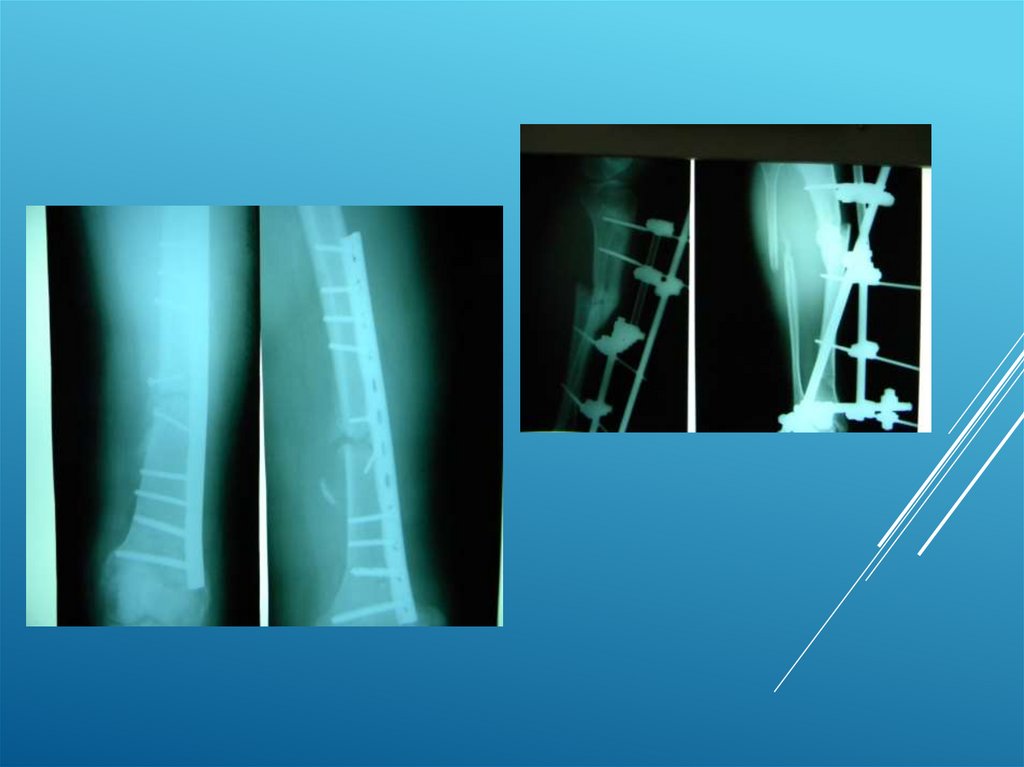

Пациент А. 50 лет

16.

17.

18.

19.

20.

Пациент С. 28 лет

21.

22.

23.

24.

25.